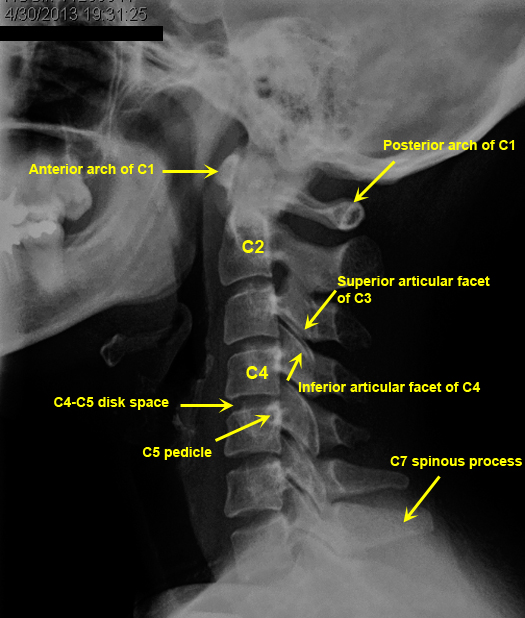

Plain Films of Skull and Spine